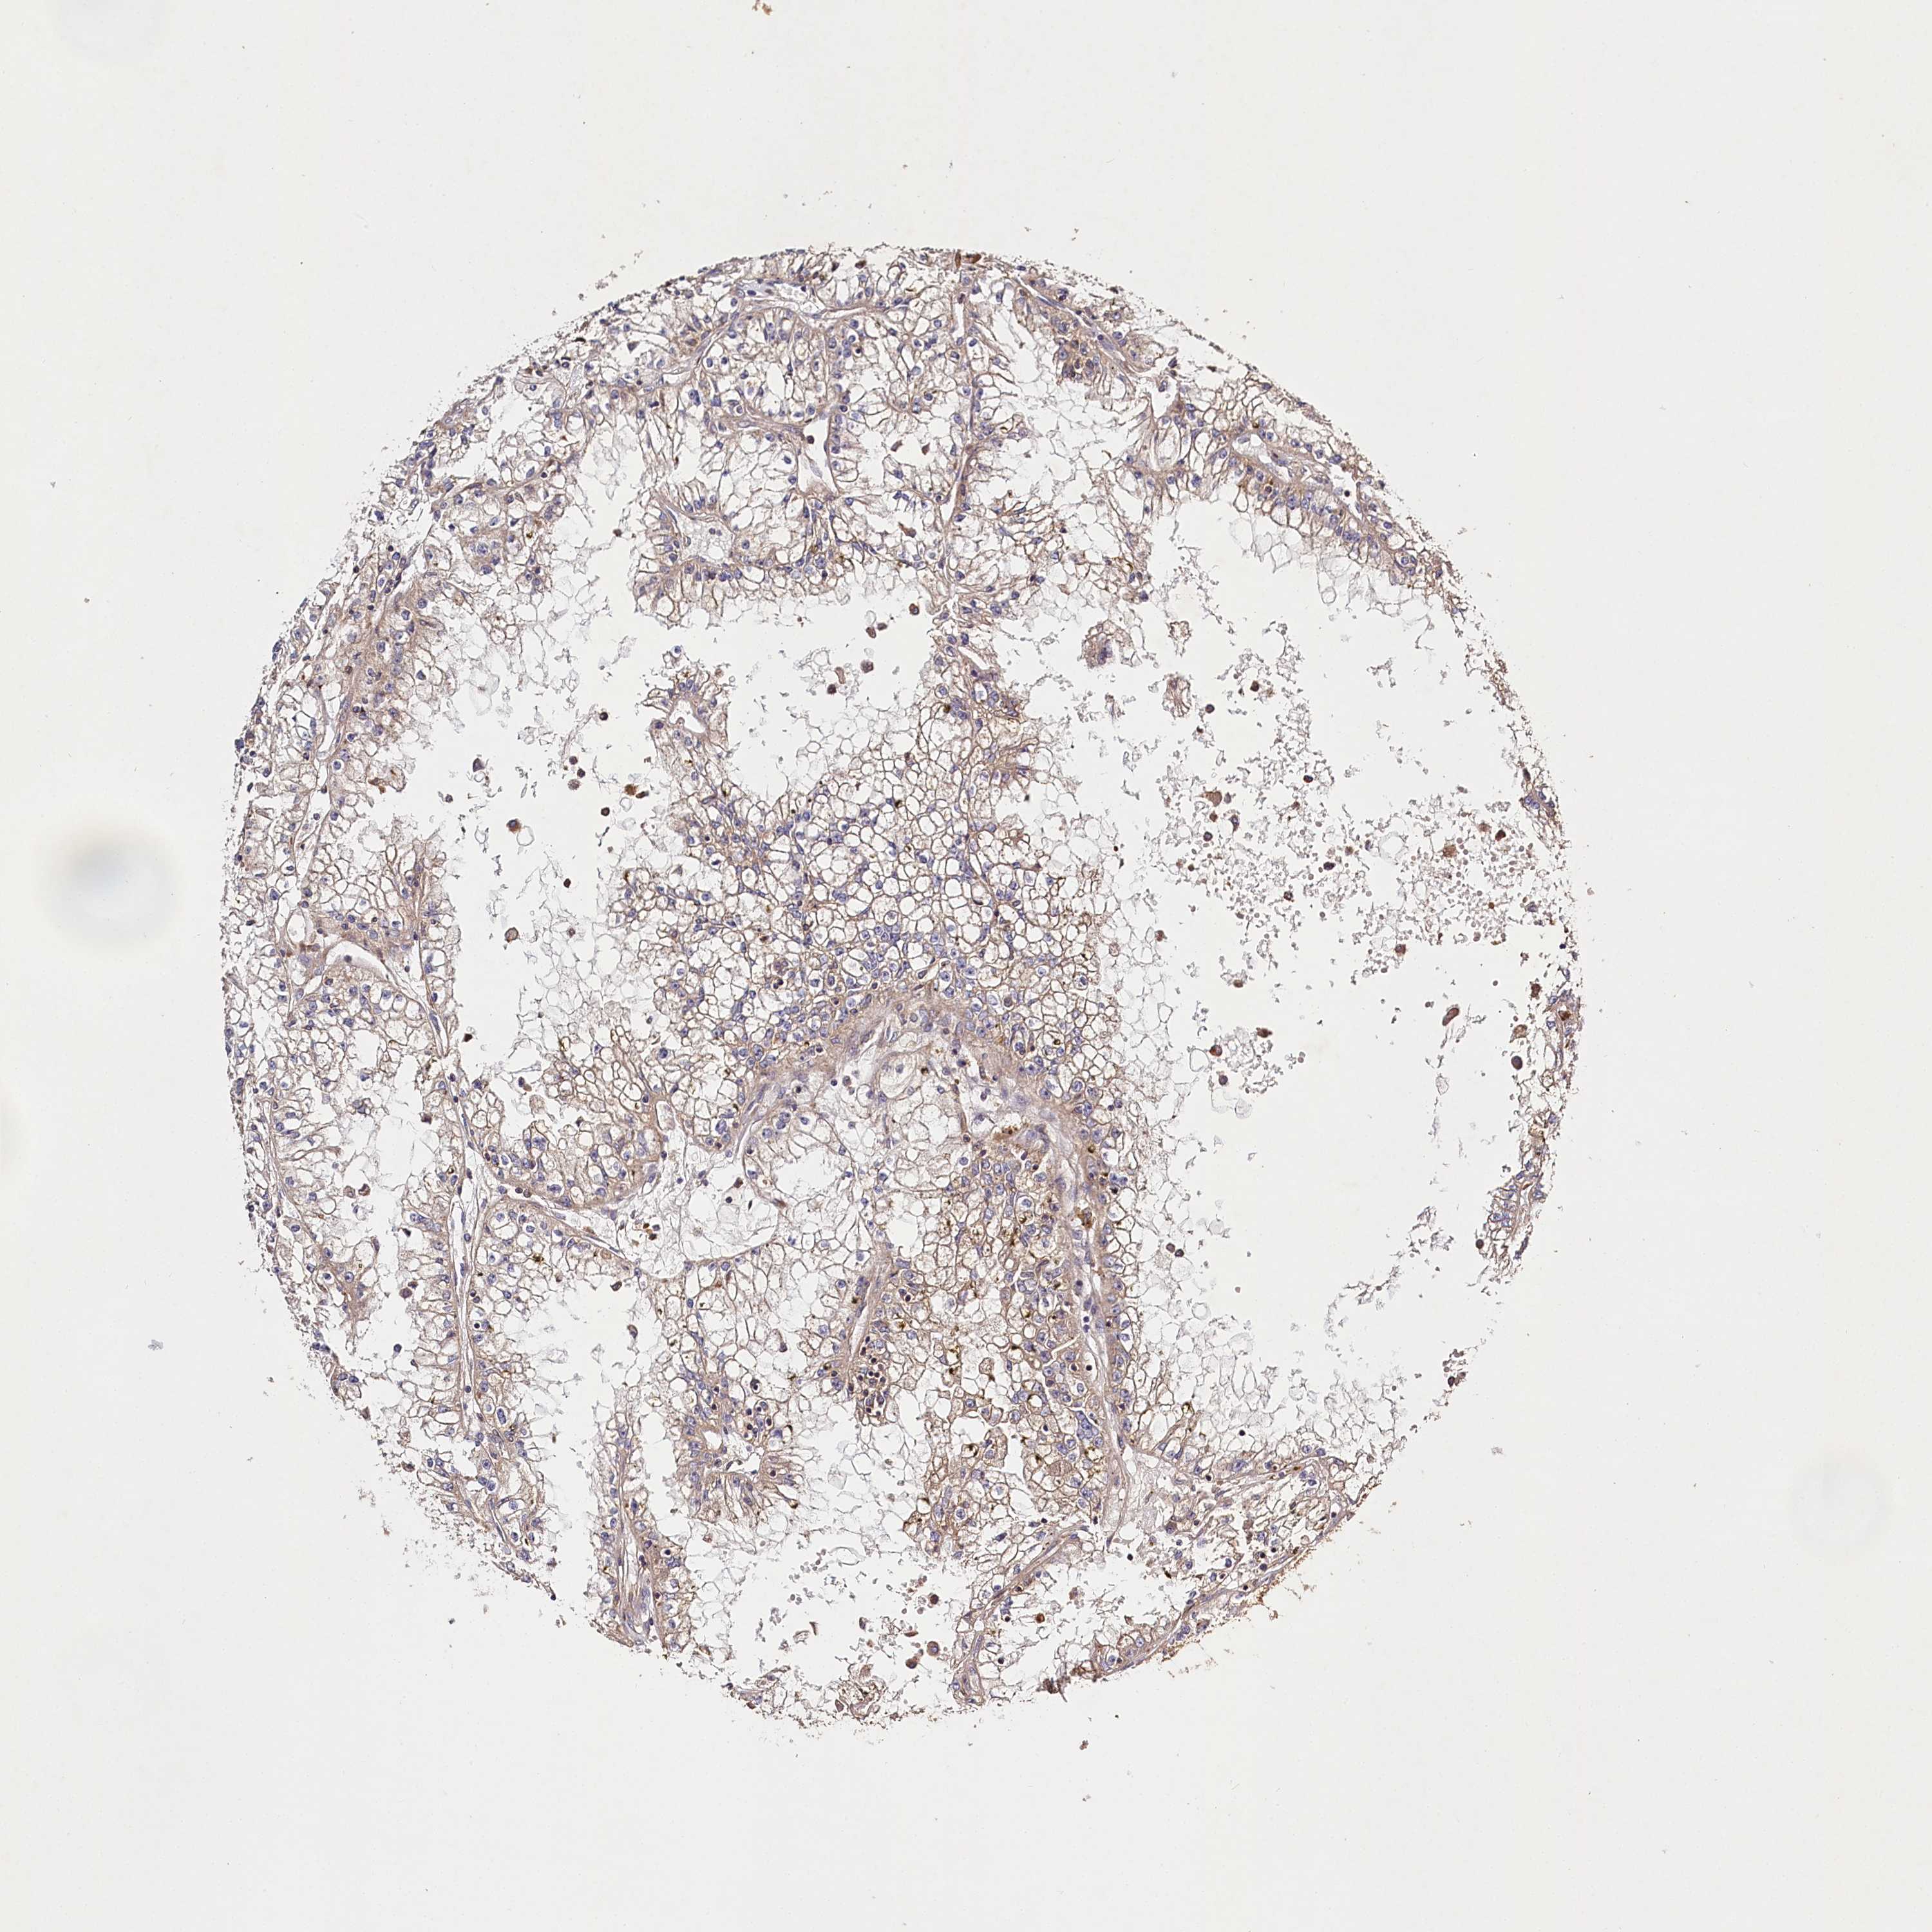

KIDNEY RENAL PAPILLARY CELL CARCINOMA (TCGA) - Interactive survival scatter ploti

LSS is not prognostic in Kidney Renal Papillary Cell Carcinoma (TCGA)

Best expression cut offi

Based on the FPKM value of each gene, patients were classified into two groups and association between prognosis (survival) and gene expression (FPKM) was examined. The best expression cut-off refers the FPKM value that yields maximal difference with regard to survival between the two groups at the lowest log-rank P-value. Best expression cut-off was selected based on survival analysis .

When clicking on this number, the vertical dashed line indicating cut-off, the interactive survival plot, and the Kaplan-Meier curve will be adjusted to show results based on the best expression cut-off.